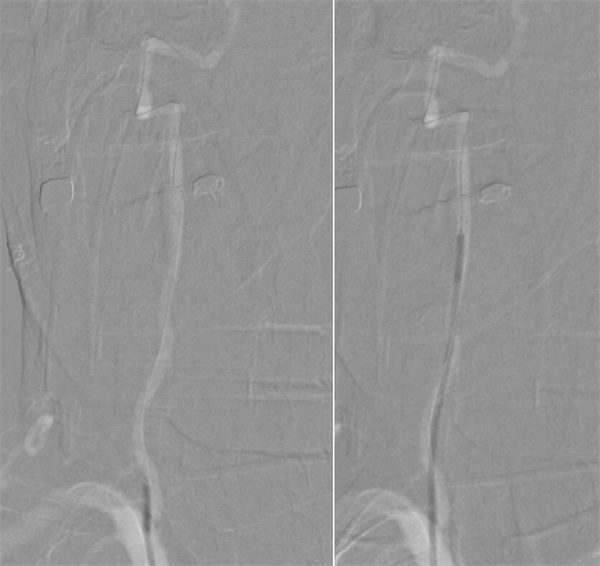

第三步,解除狭窄,恢复血流。选择合适尺寸的球囊扩张式支架,精准释放于右侧椎动脉起始部狭窄段。

第四步,最终验证。再次造影显示:狭窄消失,支架位置良好。动脉瘤不显影,弹簧圈致密填塞。